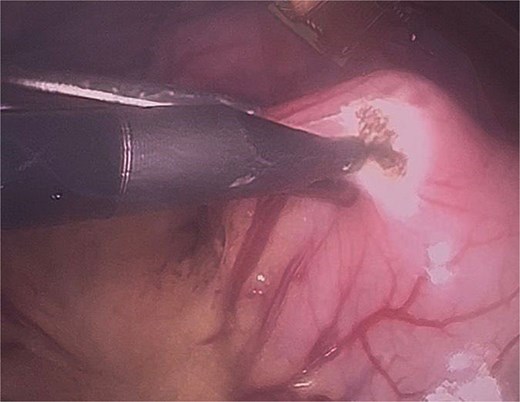

Initial gastrotomy beginning at the antral region and extending longitudinally toward the pylorus (without compromising it).

Identification of the bezoar after gastrotomy, revealing a large amount of contaminated trichobezoar material.